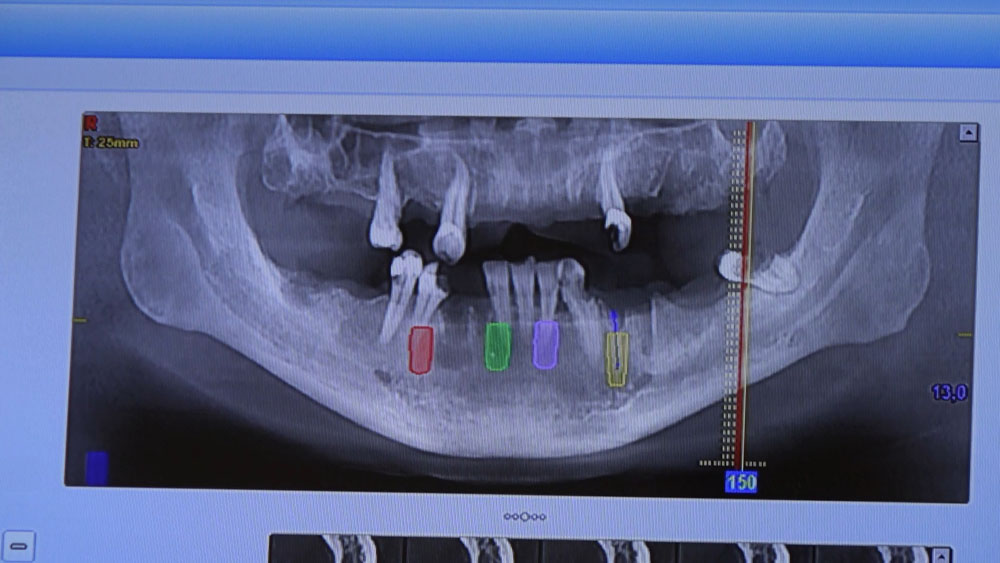

Pierwsza trzydniowa sesja odbyła się w ostatni weekend. Seminarium piątkowe i sobotnie poświęcone było chirurgii stomatologicznej. Rozpoczęły je wykłady oraz obserwacja zabiegów na żywo. Stanowiły one preludium do zabiegu szkoleniowego przeprowadzonego przez kursantów pod kontrolą dr n. med. Violetty Szycik. Wykonano trójprzestrzenną diagnostykę radiologiczną tomografem komputerowym New Tom 5G i precyzyjnie zaplanowano zabieg. Polegał on na usunięciu sześciu zębów z natychmiastową implantacją czterech implantów i regeneracją kości. Został przeprowadzony z pełnym powodzeniem. W programie tego seminarium odbyły się także ćwiczenia praktyczne chirurgicznego cięcia i szycia.